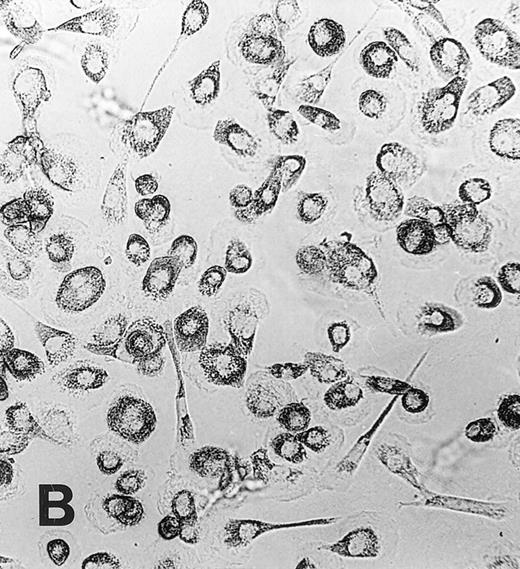

Monocyte to macrophage maturation.During culture in medium Ultradoma-PF supplemented with 10% human serum, monocytes acquired the characteristic morphological features of maturating macrophages, whereas not much change in morphology was observed during culture with medium alone (Fig 1). Viability of freshly isolated monocytes was 98% or more and decreased during 1 week of culture to 85% to 90% (without serum) and 94% to 98% (with serum), respectively. Similar to observations made by others,38 a relatively wide variability was found between different experiments regarding loss of cells in the serum free preparations. Since this did not significantly influence the extent of MGC formation, we made no further attempts to quantify this loss.

Maturation of monocytes into macrophages. Monocytes were cultured in the protein-free medium Ultradoma-PF without (A) or with (B) 10% human serum. In the presence of serum, the cells acquire the typical morphologic features of cultured macrophages. Photographs were taken on day 6 of culture. Giemsa staining, original magnification × 50.